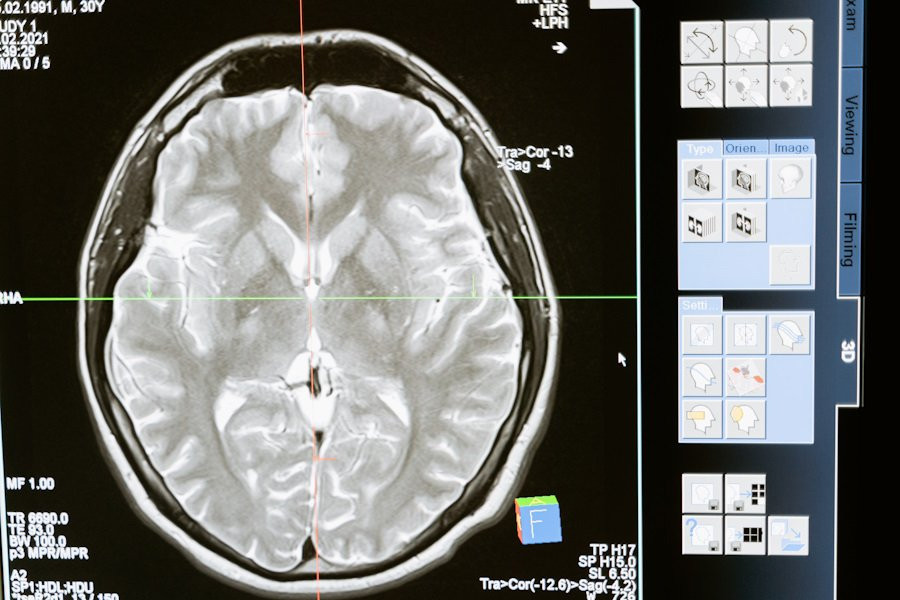

Ученые из  Washington University in Saint Louis и University of California обнаружили, что небольшие участки мозга могут находиться в состоянии микродремоты, в то время как остальная часть мозга остается бодрствующей. Открытие, опубликованное на портале Nature Neuroscience, проливает свет на ранее неизвестные свойства сна и бодрствования.

Исследование показало, что наиболее надежные сигнатуры состояний мозга обогащены ритмами от 0,1 до 20 Гц. В рамках работы ученые рассматривали возможность того, что фундаментальная единица состояния мозга может иметь масштаб миллисекунд и микрометров. Используя нейронную активность высокого разрешения, зарегистрированную в десяти областях мозга мыши на протяжении 24 часов, исследователи обнаружили, что состояния мозга надежно идентифицируются благодаря быстрой активности.

Состояния сна и бодрствования можно классифицировать на основе нейронной активности, измеренной в миллисекундах и микрометрах. В отличие от традиционных ритмов, это встраивание сохраняется при частотах выше 1000 Гц и остается устойчивым к различным подсостояниям и волновым ряби. Кроме того, отдельные области мозга периодически переключались между состояниями независимо от остальной части мозга, что совпадало с кратковременными изменениями в поведении.